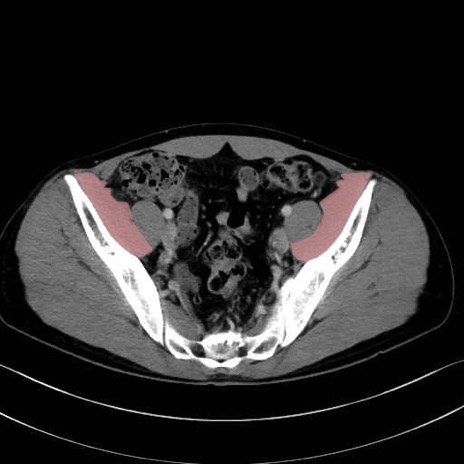

腸骨筋 (Iliacus)